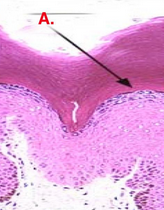

What cell layer is A? What does its presence indicate?

What is this cell layer?

Stratum spinosum

What cell layer?

Stratum basale

what makes the brownish color in the stratum basale?

red - stratum basale

blue - stratum spongiosum

black - stratum granulosum

green- stratum corneum

brownish color is keratinotinocytes